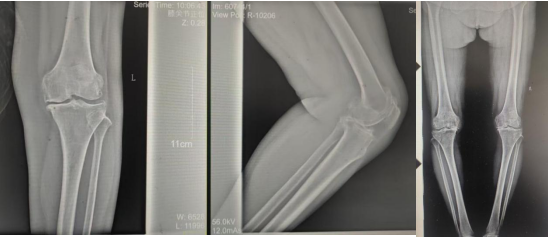

术前影像资料

张女士于10年前劳累后左膝疼痛,,,,,,,,干活后疼痛较重,,,,,,,,阴雨天及受凉时疼痛明显,,,,,,,,行走时可闻及关节内异响,,,,,,,,时有“打软腿”现象,,,,,,,,曾到附近多家医院诊治,,,,,,,,给予膝关节针灸、膏药外贴、口服药物等“保守”治疗,,,,,,,,治疗后疼痛症状略有好转,,,,,,,,但易复发;;;;;;;;近2年患者左膝关节疼痛逐渐加重,,,,,,,,行走跛行,,,,,,,,下蹲及上下楼梯困难,,,,,,,,活动时疼痛明显,,,,,,,,休息、保守治疗后疼痛无明显好转。。。。。。

张女士的邻居看她上下楼如此困难,,,,,,,,日常生活都很受影响,,,,,,,,因其以前在我院看过腰椎,,,,,,,,效果良好,,,,,,,,故介绍张女士来我院找万昌胜主治医师进行咨询问诊。。。。。。万医生了解情况后带她到我院关节外科进行更专业的诊治。。。。。。关节外科门诊医师结合症状体征及影像学检查,,,,,,,,建议入院手术治疗,,,,,,,,以“左膝骨性关节炎伴膝内翻、高血压病”收住入院。。。。。。